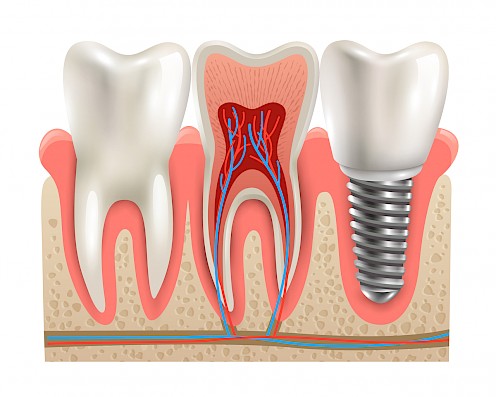

There are two main parts to an implant. The main part of the implant is the post. This part goes into your jaw where it fuses with the bone. Posts are usually made from titanium. This material is known for its durability and hypoallergenic qualities. Zirconia, which is metal-free, can also be used to make implant posts, in the rare instances the patient is allergic to titanium.

The top part of the implant is called the crown. This is the part that looks like your natural teeth. Similar to a regular dental crown, these can be made from a variety of materials. Porcelain, ceramic and metal crowns are all potential options. Porcelain can also be fused to metal for a stronger implant crown.

Dental Implants vs Removable Dentures

Dental implants are one of the most effective ways to replace teeth.

They are more stable than removable dentures.

Implants look and feel more like a natural set of teeth.

Fixed implants allow the wearer to feel the texture of food when eating.

They will always fit - there’s never a need to have them readjusted or relined.

Fixed implants don’t have to be removed at night for cleaning.

The stimulation they provide to the jaw helps to prevent further bone loss.